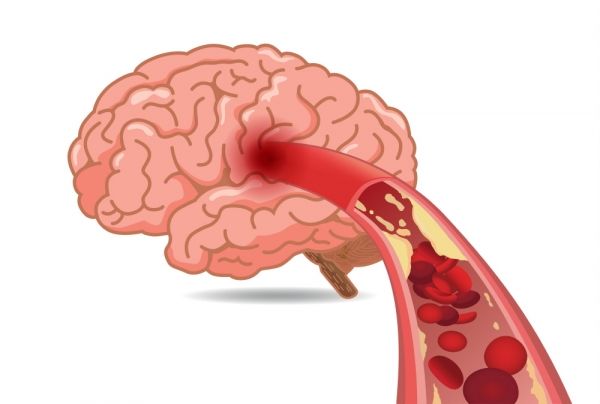

뇌혈관이 막히거나 터지는 질환을 부르는게 뇌졸중이고 그 중 뇌혈관이 막히는게 뇌경색 그리고 뇌혈관이 터지는 것을 뇌출혈이라고 합니다. 뇌졸중은 영구적인 손상이 많다고 하며 증상에 따라 전신이나 육체 일부 기능이 마비되는 등의 극심한 후유증이 남는 무서운 질병입니다 오늘은 뇌경색 초기증상에 대하여 알려드리도록 하겠습니다.

허혈성 뇌졸중은 발생 기전에 따라 대혈관 질환에 의한 뇌경색, 심인성 뇌경색 또는 심인성 뇌경색, 소혈관 질환 또는 틈새 뇌경색, 기타 드문 이유가 되는 것에 의한 뇌경색으로 나누어져요. 에피소드는 일정 기간 동안 증상이 완전히 가라앉는 경우입니다.

허혈성 뇌졸중의 대표적인 이유가 되는 것은 고혈압, 당뇨병, 고지혈증 등으로 인해서 뇌에 혈액을 전달하는 혈관에 동맥경화(동맥경화)가 발생하여 뇌로 가는 혈류를 차단하는 것입니다.